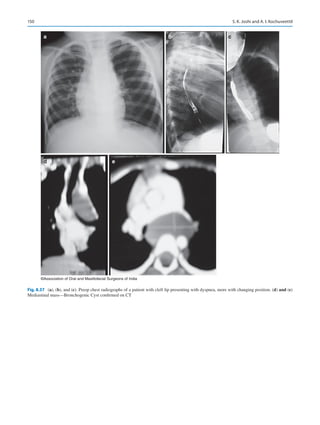

India Extraordinary No DE 22–2007, Government of India, dated

20th November 2007, pp 56–68.

5.	Nayak K. Oral and maxillofacial surgery: It’s future as a specialty. J

Maxillofac Oral Surg. 2011;10(4):281–2.